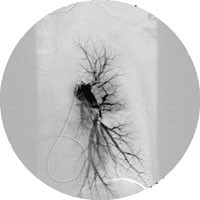

Spiral-CT av thorax viste massiv lungeembolisme med ein stor, sentral embolus i høgre grein av arteria pulmonalis og fleire perifere embolusar i begge lunger (fig 1). Ultralydundersøking av lårvener bilateralt viste ingen teikn til venetrombose. I same seanse som den trombolytiske behandlinga vart det gjort cavagrafi, som ikkje viste teikn til trombose i bekkenvener eller v. cava, og pulmonal angiografi, som stadfesta forholda i lungekretsløpet.

Ny spiral-CT neste dag viste opne arteriar bilateralt, bortsett frå ein underlappsarterie dorsalt på høgre side, der det framleis var små trombemassar (fig 2).